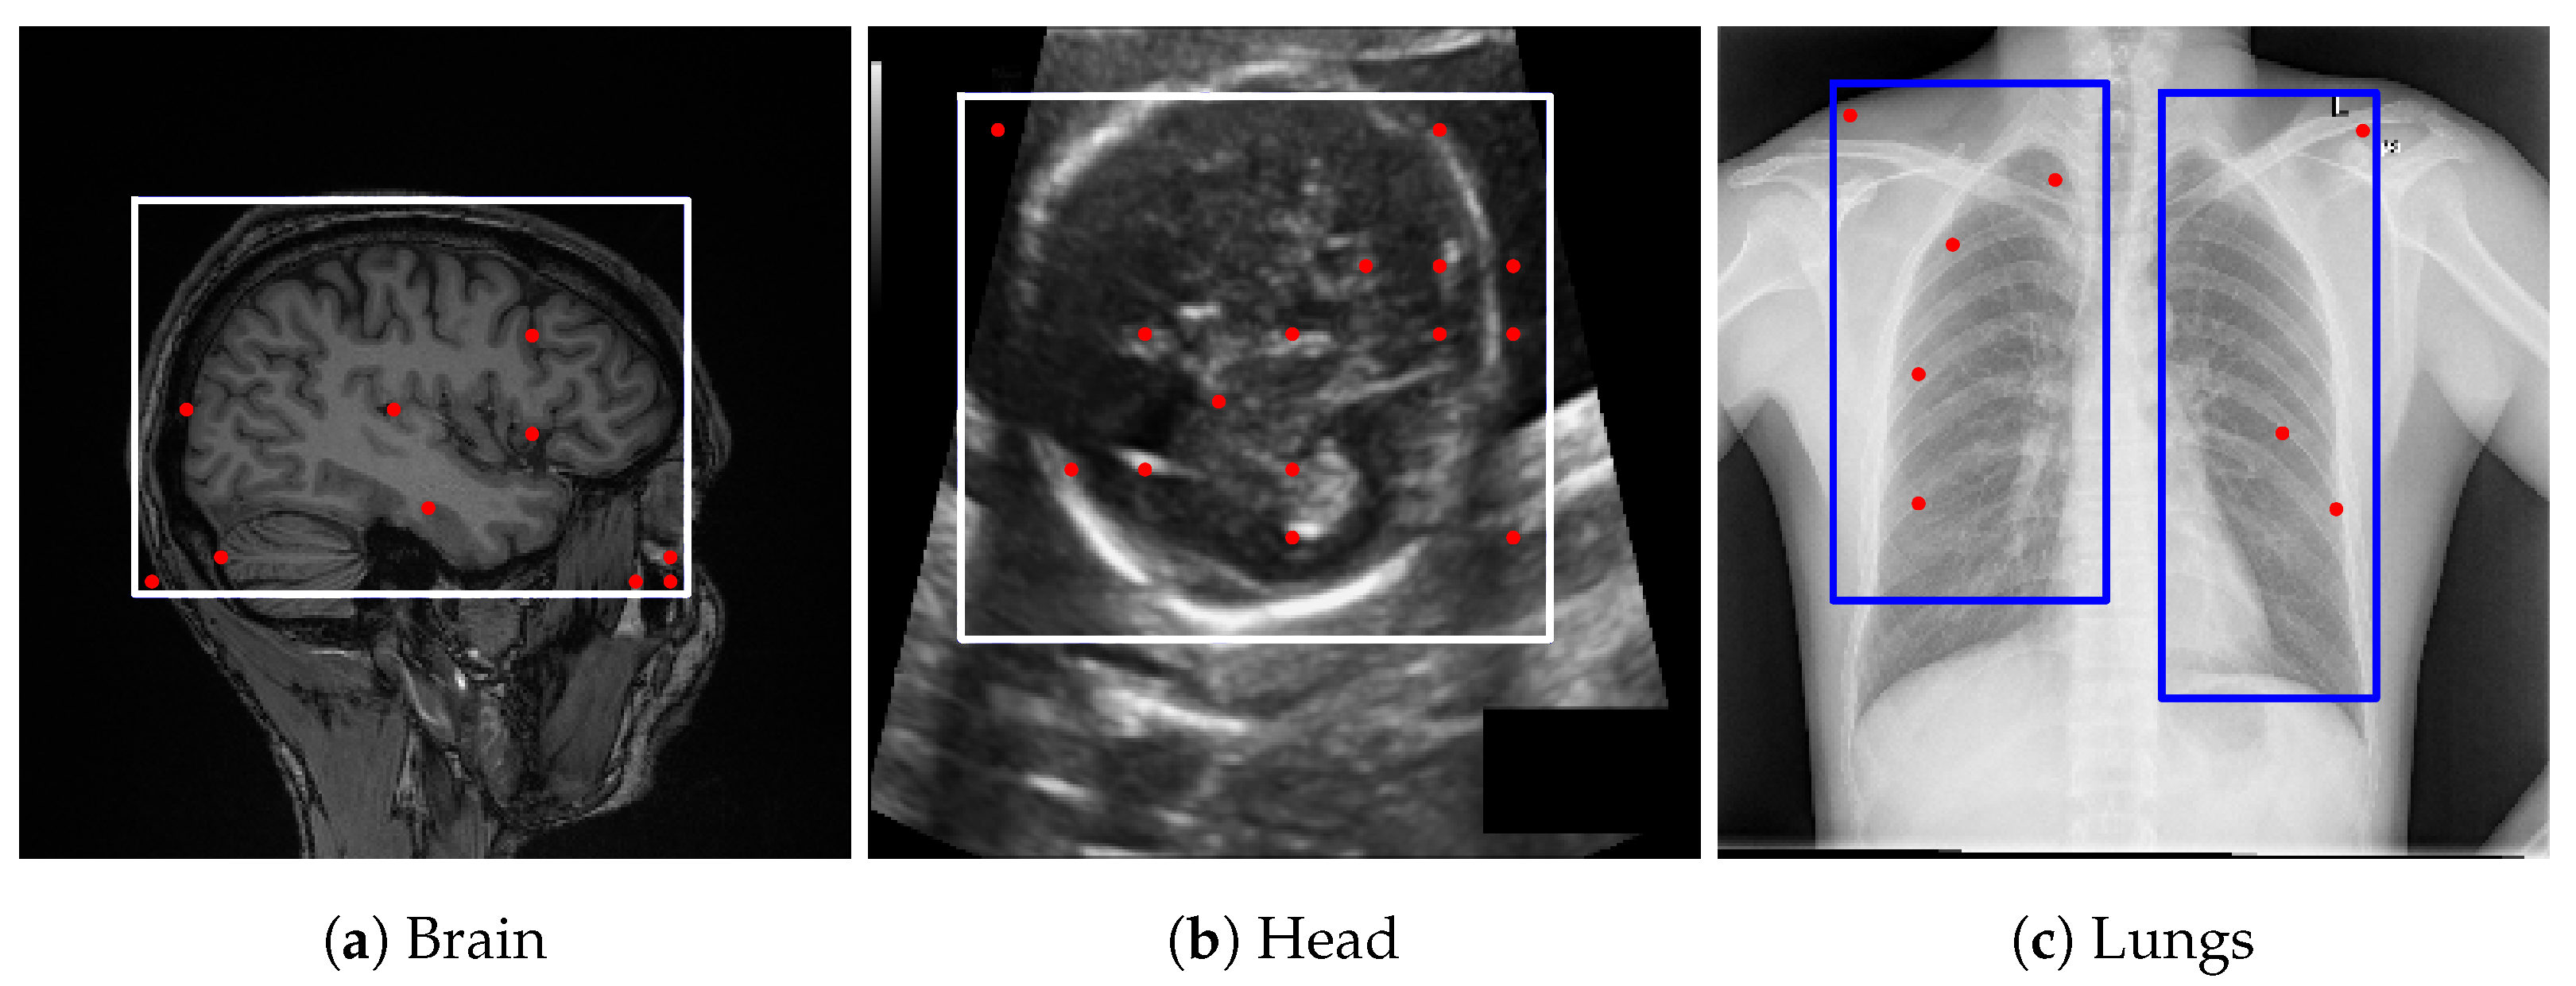

Figure 2. Examples of lung bounding box estimations generated by different models: LLaMA-4-Maverick-17B-128E, GPT-4o, and Gemini Pro 2.5. The blue rectangles indicate the bounding-box prompts, and the red dots represent the point prompts. Both are provided as inputs to the Segment Anything Model (SAM) to generate segmentation candidates.

GPT-4o [13] demonstrated performance comparable to Gemini Pro 2.5 [9] in our internal evaluations; however, Gemini Pro 2.5, available from Google, was chosen for downstream experiments due to its consistent accuracy, stable API access, and available research funding for sustained API usage. It also outperformed LLaMA-based models, as shown in Figure 2. Model outputs were returned in JSON format and integrated directly into our segmentation pipeline. While the bounding box estimations generated by Gemini across multiple datasets were not sufficiently precise to serve as final segmentations, they consistently localized the region of interest. Despite occasional boundary inaccuracies, these estimations provided reliable spatial priors that effectively guided the SAM model towards more accurate segmentations, as illustrated in Figure 3.

4.5.4. Prompt Engineering and Choice of Large Vision-Language Models for Bounding Box Estimation

To derive reliable bounding box priors, we designed structured prompts that explicitly defined both the target anatomical structures and the spatial constraints of the bounding box. The final prompts used in our pipeline are provided in Appendix B. These prompts were tested across several LVLMs, including maverick-llama-4, GPT-4V, and Gemini Vision. While multiple models could generate bounding boxes, we selected Gemini Pro 2.5 for its consistent alignment with regions of interest and compatibility with available computational resources. In contrast, alternative models often produced loose or misaligned boxes, which degraded downstream segmentation accuracy. Representative bounding box results from different models with the same prompt are shown in Figure 2, underscoring the importance of prompt engineering and the sensitivity of the pipeline to LVLM choice.